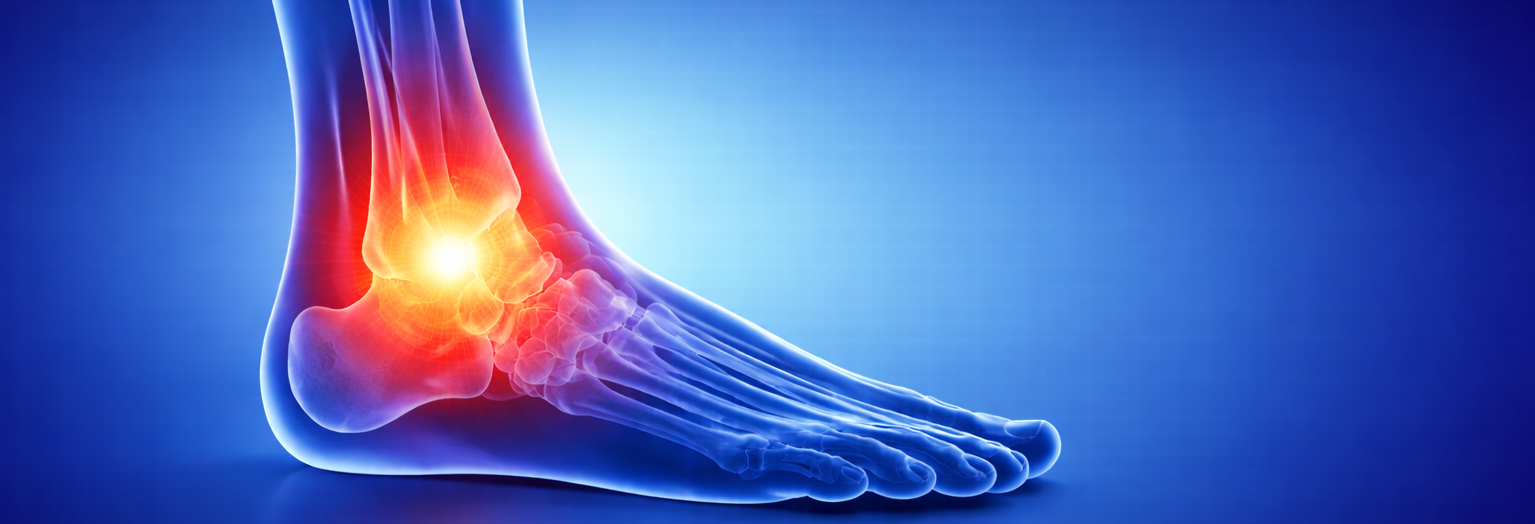

Сложный сустав, обеспечивающий опорную и двигательную функцию. Работаем с травмами связок, сухожилий, переломами лодыжек, воспалительными заболеваниями и хроническими болевыми синдромами.

Голеностопный сустав — сложный анатомический комплекс, обеспечивающий опорную и двигательную функцию при ходьбе, беге, прыжках и резких изменениях направления движения. Он ежедневно воспринимает значительные нагрузки и играет ключевую роль в устойчивости всего опорно-двигательного аппарата.

Нарушения в работе голеностопного сустава нередко проявляются болью, отёком, ощущением нестабильности или ограничением подвижности. При этом проблема может формироваться как вследствие острой травмы, так и постепенно — на фоне повторяющихся перегрузок и недостаточного восстановления.